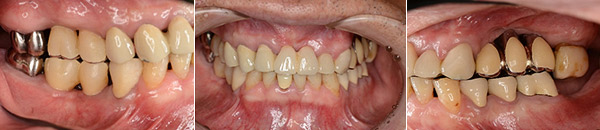

67歳男性の方です。初診時は、本人も上顎の歯すべて抜歯になり、総入れ歯を覚悟していたそうです。できる限り天然歯を温存し、治療は1年8ヶ月という長い期間かかりましたが、包括的な総合的治療により患者様に大変喜んで頂けるゴールを迎える事が出来、先日メンテナンスへ移行しました。

この患者様は、当医院まで片道1時間半もかけて来院して頂いていました。いつも明るく元気に前向きに治療を受けられていた患者様の努力が良い結果に結びついたと思います。

治療終了時